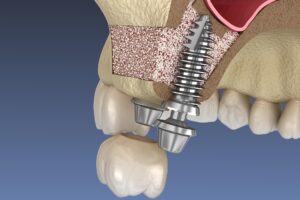

インプラントを埋める部分の上顎洞の底の部分を骨折させて挙上させ、それによってできたスペースに骨となる材料を満たしてインプラントを埋める厚みを確保します。

骨がかなり薄いケースや、同じ側の奥歯に複数のインプラントを埋め込む場合に行われます。上顎洞の骨を歯茎を切開することによって露出させ、骨の一部を開けて上顎洞の粘膜を剥離して持ち上げ、そこにできた部分に骨となる材料を満たして大量の骨を作り出し、インプラント治療を可能にします。

こちらは上の二つの方法と違い、骨の材料となる人工骨の移植を行わない治療法です。上顎洞など、骨の中の大事な組織を避けて斜めにインプラントを埋め込みます。